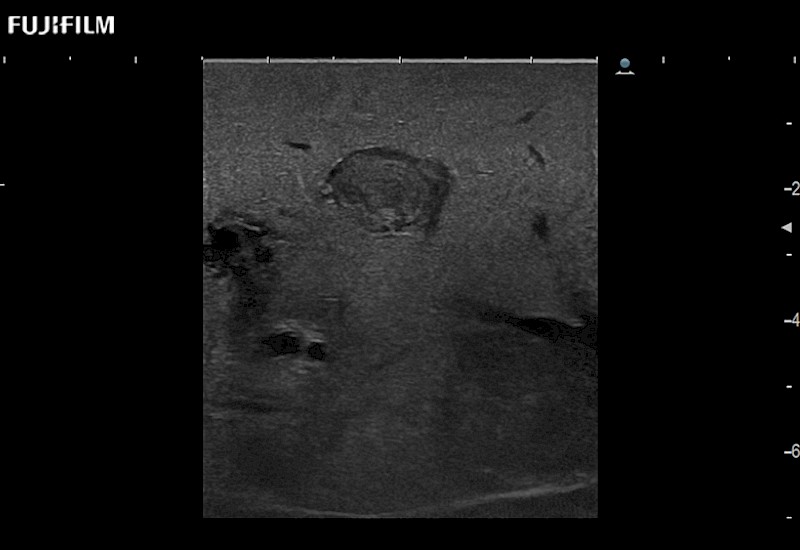

Exclusive linear array robotic surgery transducer.

Features:

Main Specifications: